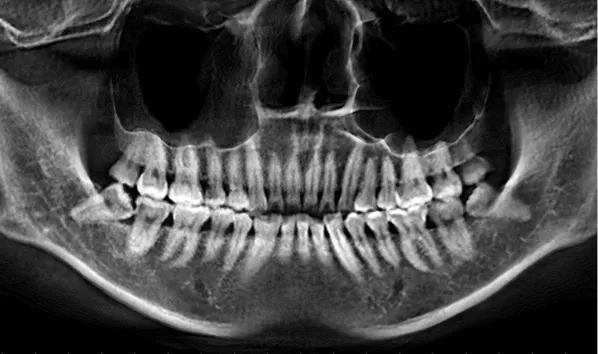

Rayons X avant le traitement

[Radiographie panoramique/Céphalogramme latéral]